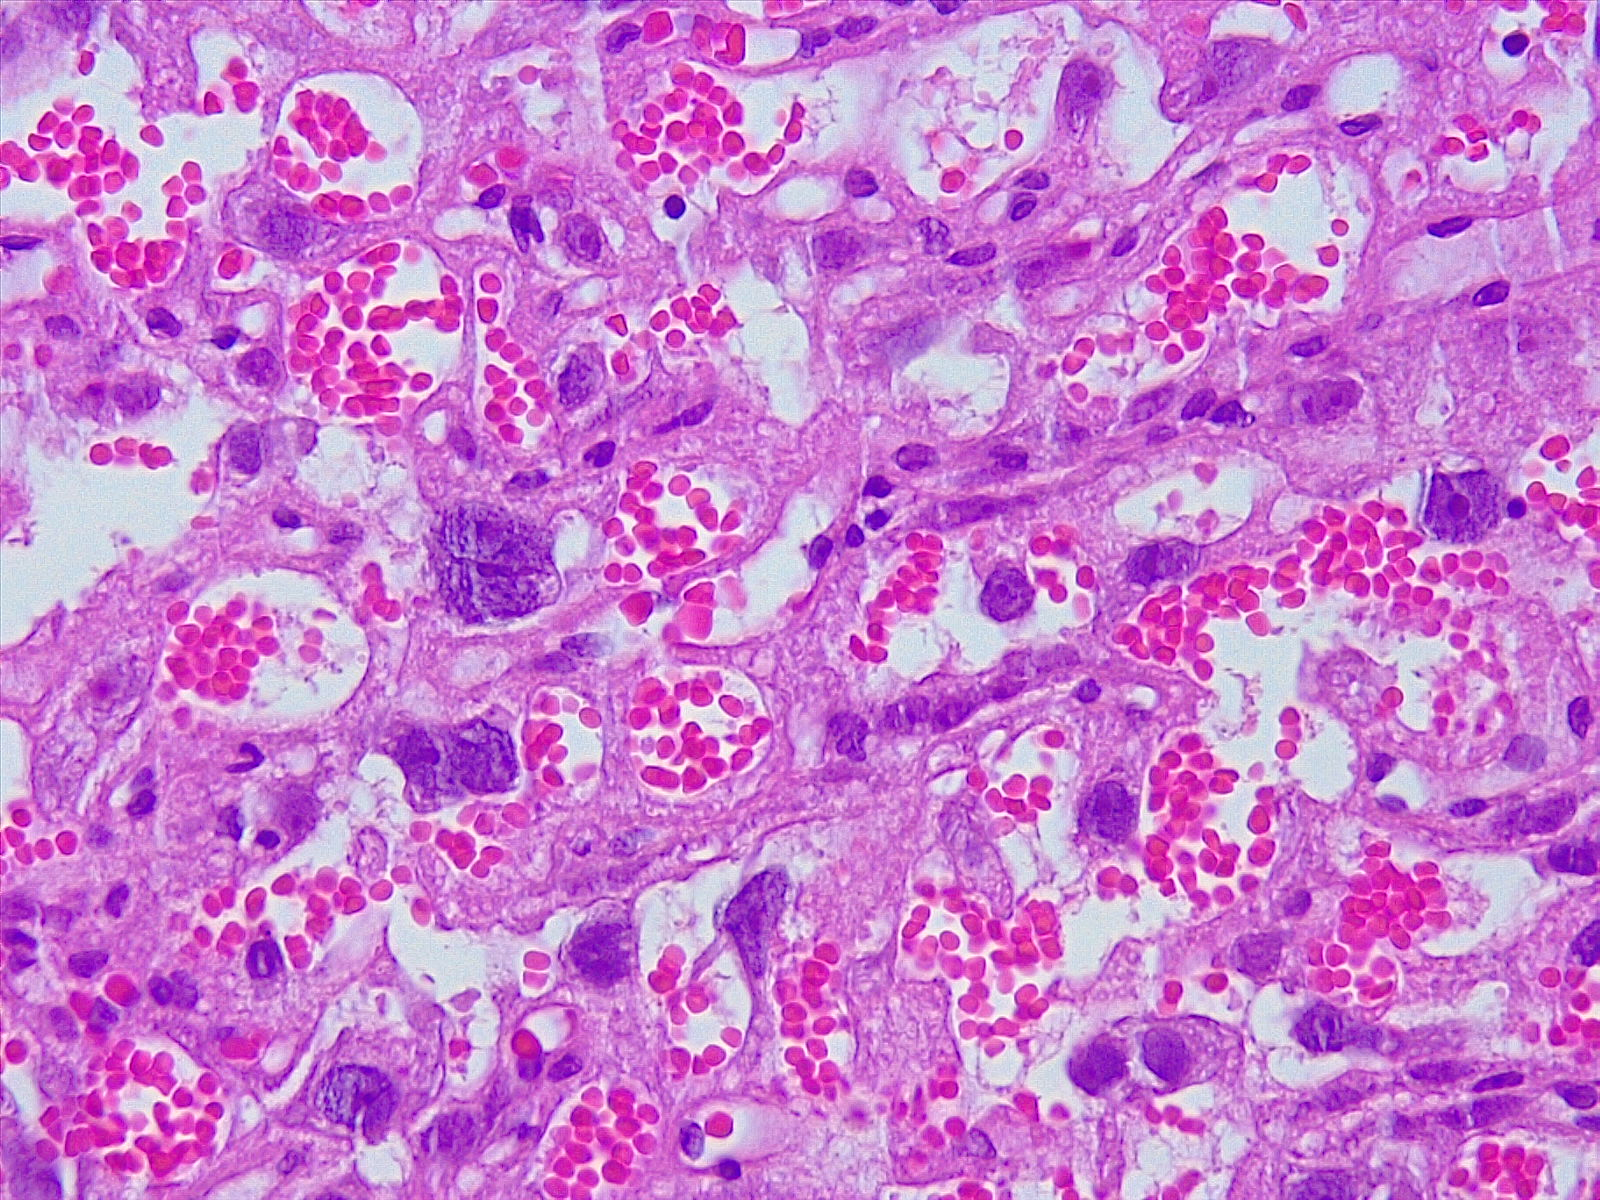

Francisca Villarroel expresó que “he visto mucha motivación de los estudiantes por aprender ciencias, conocer cómo se forma nuestro cuerpo, además de mucho agradecimiento de ellos por la actividad, ya que para muchos era la primera vez que utilizaban un microscopio y podían observar muestras histológicas en el caso de mi módulo”.